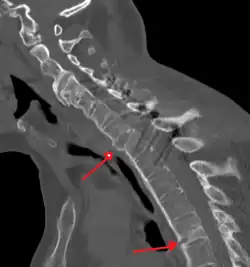

X-rays

The earliest changes demonstrable by plain X-ray shows erosions and sclerosis in sacroiliac joints. Progression of the erosions leads to widening of the joint space and bony sclerosis. X-ray spine can reveal squaring of vertebrae with bony spur formation called syndesmophyte. This causes the bamboo spine appearance. A drawback of X-ray diagnosis is the signs and symptoms of AS have usually been established as long as 7–10 years prior to X-ray-evident changes occurring on a plain film X-ray, which means a delay of as long as 10 years before adequate therapies can be introduced.[25]

Lateral X-ray of the neck in ankylosing spondylitis

CT scan showing bamboo spine in ankylosing spondylitis